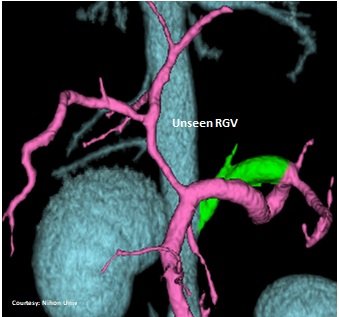

INTRAHEPATIC ENTRANCE

“aLGC +RGV”

(Aberrant Left Gastric – Caval shunt with Right Gastric Vein contribution)

“aLGC +SGV”

(Aberrant Left Gastric – Caval shunt with Short Gastric Vein contribution)